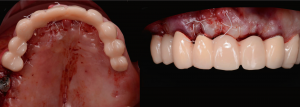

Second set of provisional restorations printed with GC Temp PRINT (medium shade) using the Asiga Max UV 3D printer. Fig. 13

Completed provisional crowns, implant retained crowns and bridge, characterized with OPTIGLAZE color (GC) – Dental technician: Brad Groblar, Oral Dynamics, New Zealand. Fig. 14

Completed provisionals fitted onto the printed models to allow the refinement of the contact points and occlusal contacts. Fig. 15 (i, ii)